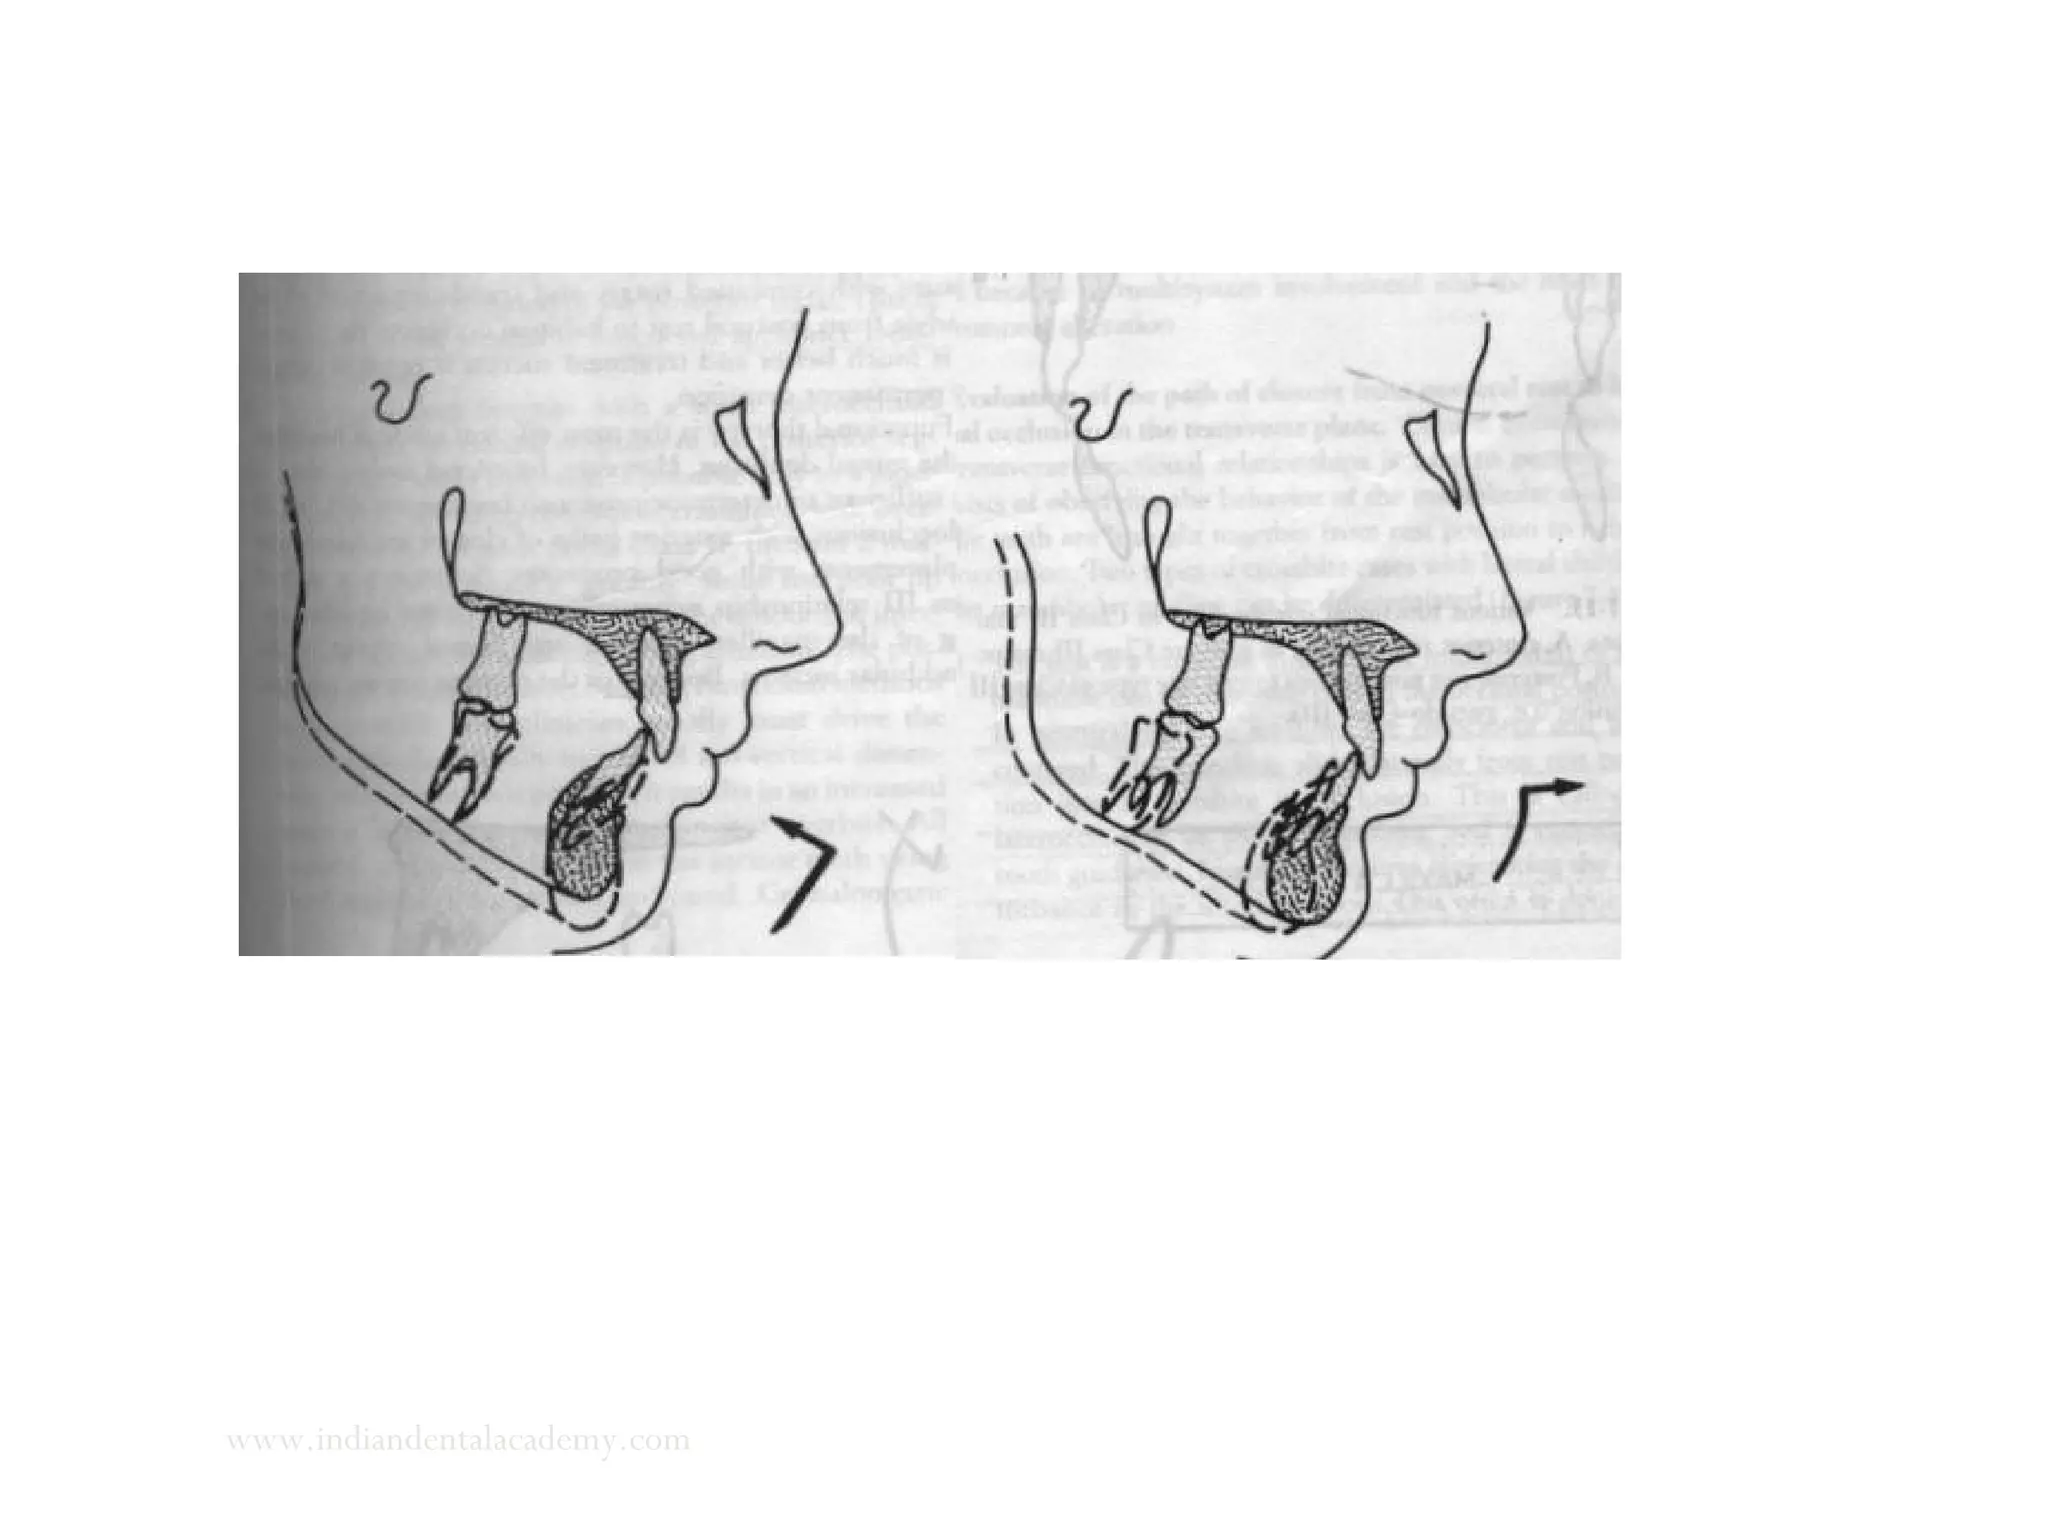

Evaluation of the path of closure from postural rest to occlusion in

sagittal plane

www.indiandentalacademy.com